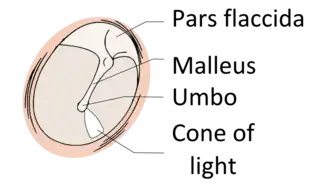

The eardrum is divided into two general regions: the pars flaccida and the pars tensa.[3] The relatively fragile pars flaccida lies above the lateral process of the malleus between the Notch of Rivinus and the anterior and posterior malleal folds. Consisting of two layers and appearing slightly pinkish in hue, it is associated with Eustachian tube dysfunction and cholesteatomas.[4]

The larger pars tensa consists of three layers: skin, fibrous tissue, and mucosa. Its thick periphery forms a fibrocartilaginous ring called the annulus tympanicus or Gerlach's ligament.[5] while the central umbo tents inward at the level of the tip of malleus. The middle fibrous layer, containing radial, circular, and parabolic fibers, encloses the handle of malleus. Though comparatively robust, the pars tensa is the region more commonly associated with perforations.[6]

The manubrium (Latin for "handle") of the malleus is firmly attached to the medial surface of the membrane as far as its center, drawing it toward the tympanic cavity. The lateral surface of the membrane is thus concave. The most depressed aspect of this concavity is termed the umbo (Latin for "shield boss").[7]

When the eardrum is illuminated during a medical examination, a cone of light radiates from the tip of the malleus to the periphery in the anteroinferior quadrant, this is what is known clinically as 5 o'clock.